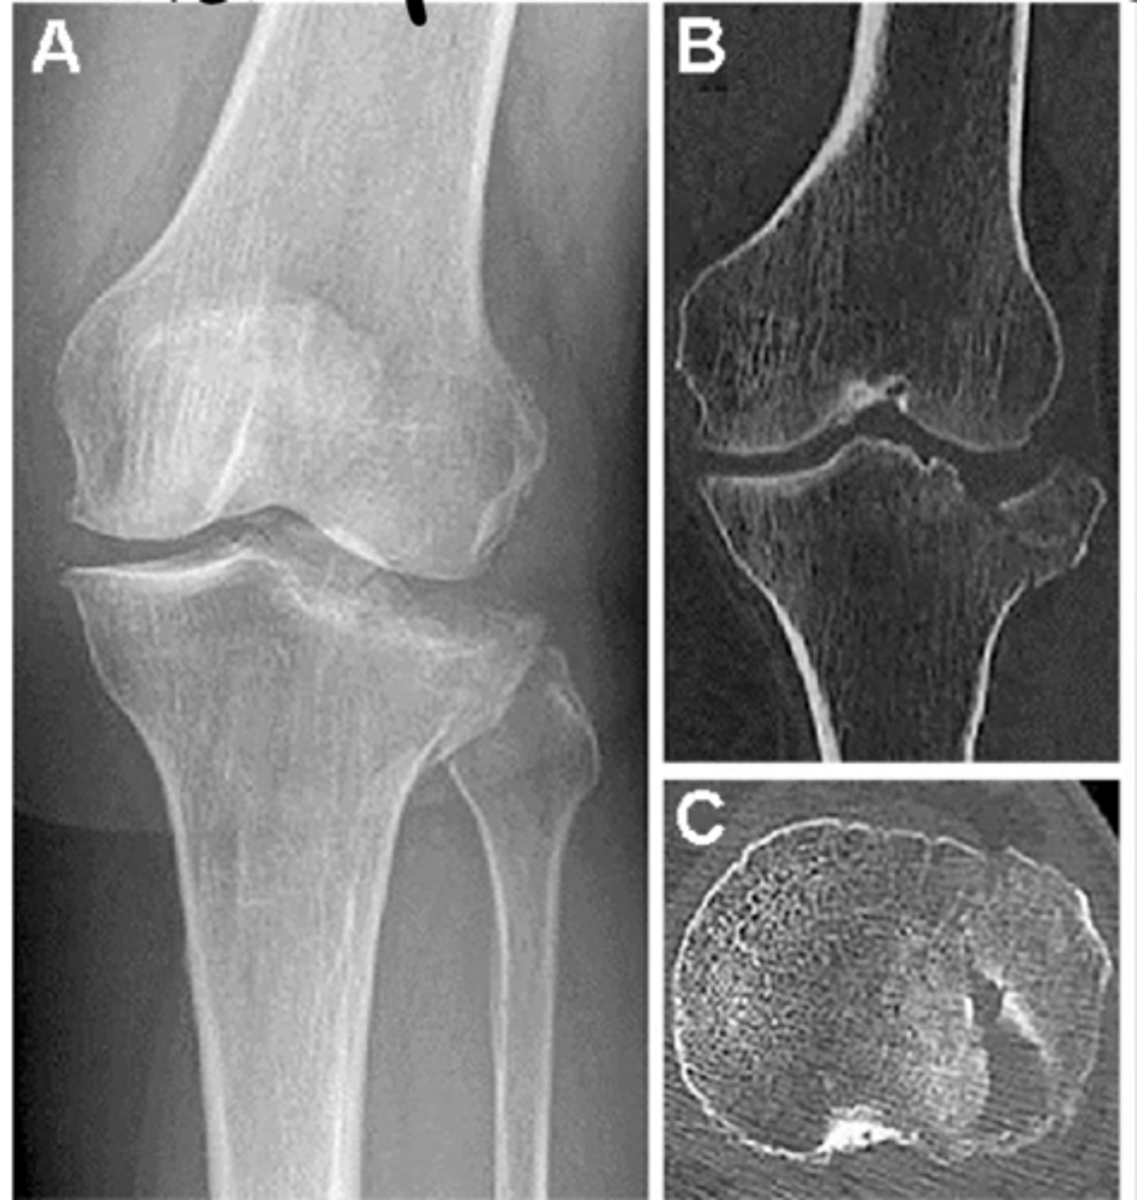

Comminuted patellar fracture

Define the pathology.

Tibial plateau fractures